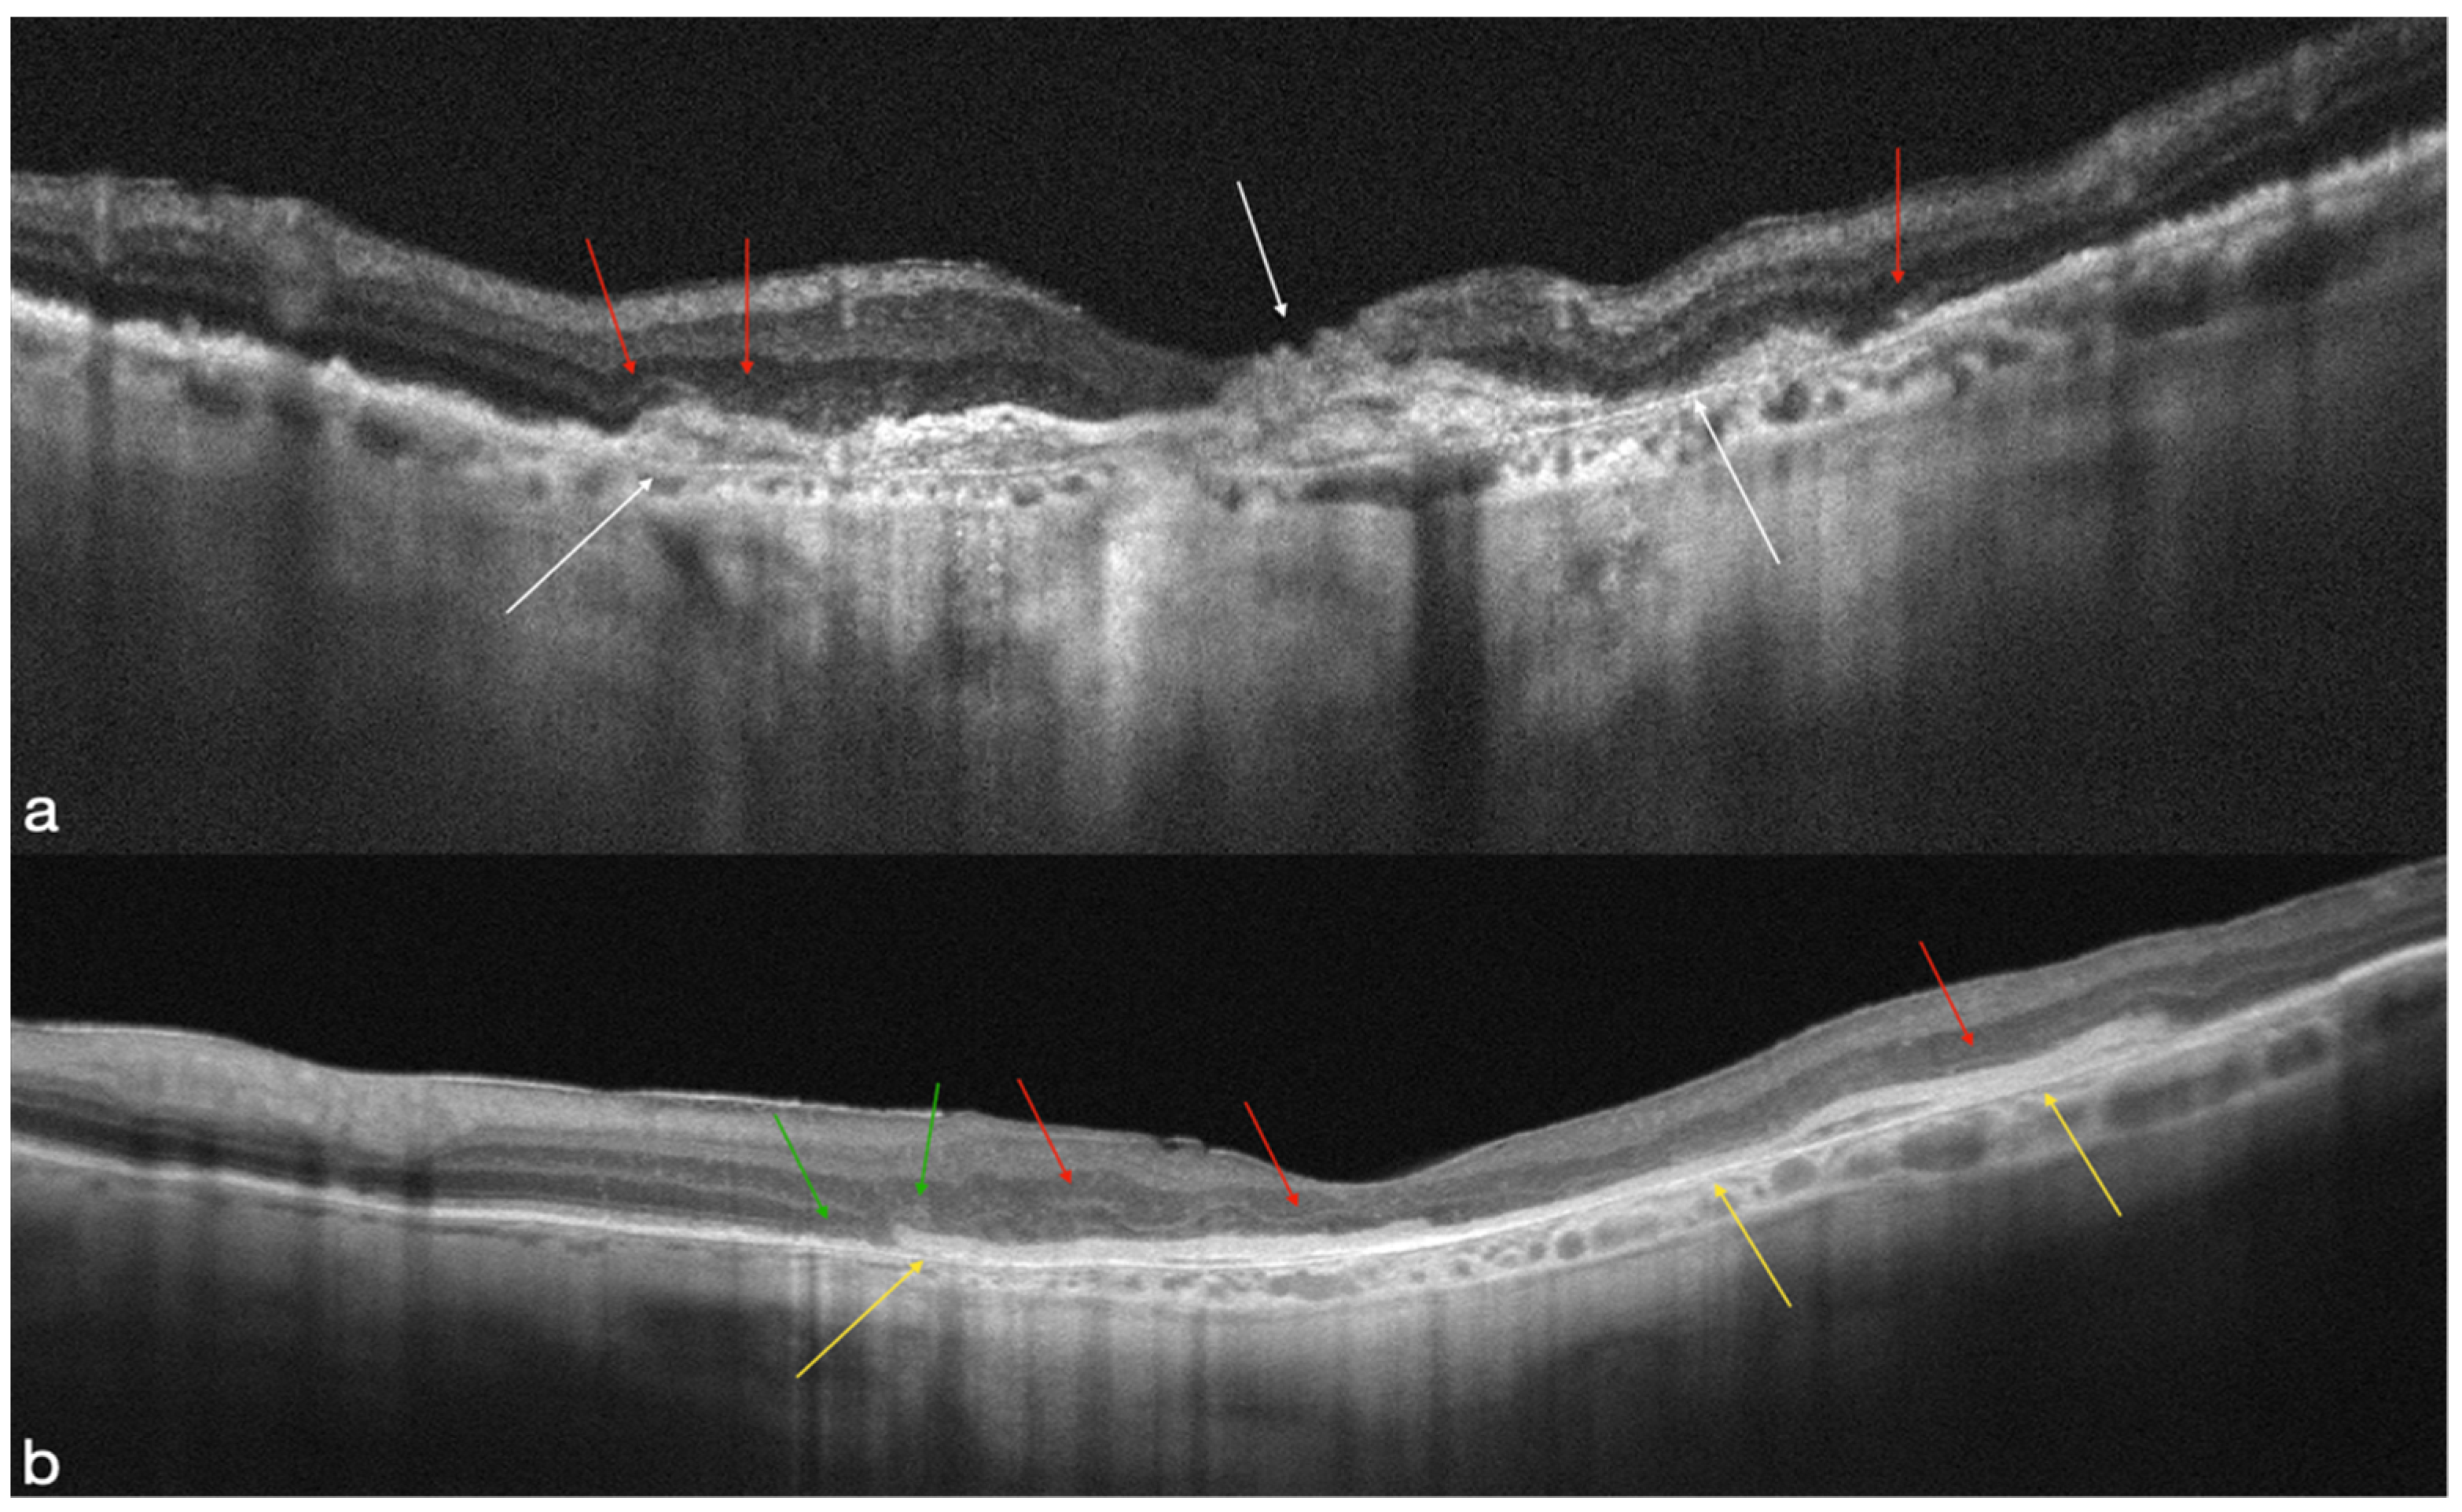

4.1. MNV-Group

4.2. Atrophic Group